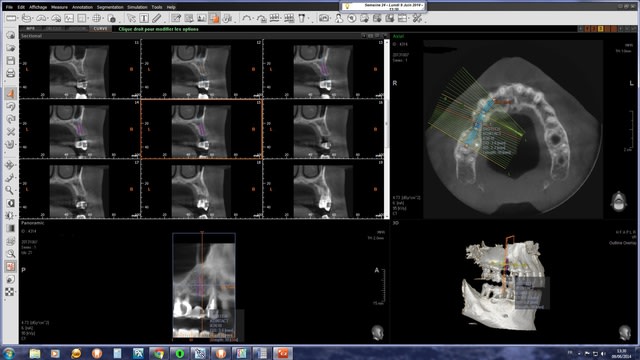

J'ai posé mercredi dernier un implant pour remplacer une 15 absente depuis des années sur un patient de 40 ans en bonne santé mais fumeur avec une parodontite chronique généralisée modérée stabilisée.

La crête étant pas mal résorbée en vestibulaire, j'ai opté pour la pose d'un implant de 3.6mm de diamètre ( biotech kontact 3.6/10) en faisant une expansion à l'aide d'ostéotomes.

La PM1 tire en effet un peu la gueule mais asymptomatique cliniquement + aucune image apicale au cbct. Aucune mobilité bien entendu. Je l'estimais conservable pour l'instant en unitaire mais trop risquée pour servir à nouveau de pilier de bridge...Et si on regarde de près, la 6 et la 7 tirent aussi "un peu" la gueule.

A l'examen clinique, il a un bel œdème au niveau de la joue mais rien de particulier au niveau du site opératoire. L'implant sonne bien mat et la percussion ne provoque aucune douleur. Palpation sensible en vestibulaire et en palatin, ce qui ne me parait pas extraordinaire à 5j post-op. RAS à la radio